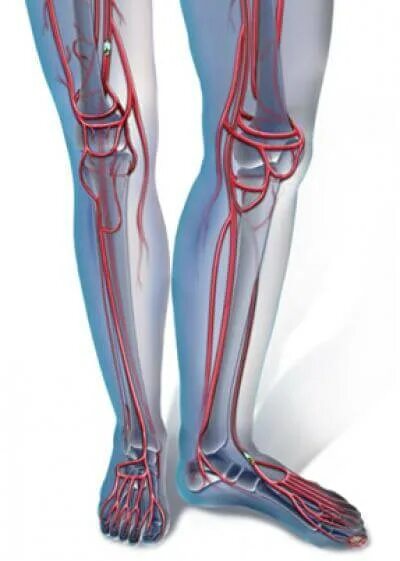

Повреждение сосудов конечностей